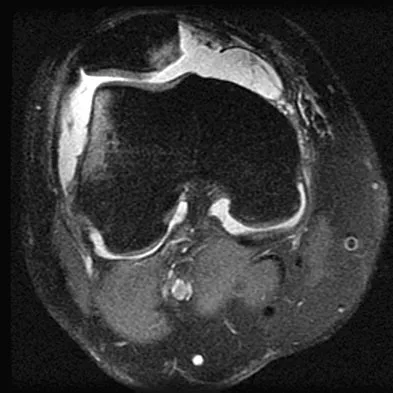

Figure 48 shows an MRI scan of the knee. The arrow is pointing to what structure?